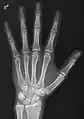

- دست - DP و مایل

پروجکشن دست چپ به واسطه dorsoplantar

پروجکشن جانبی

پروجکشن مایل